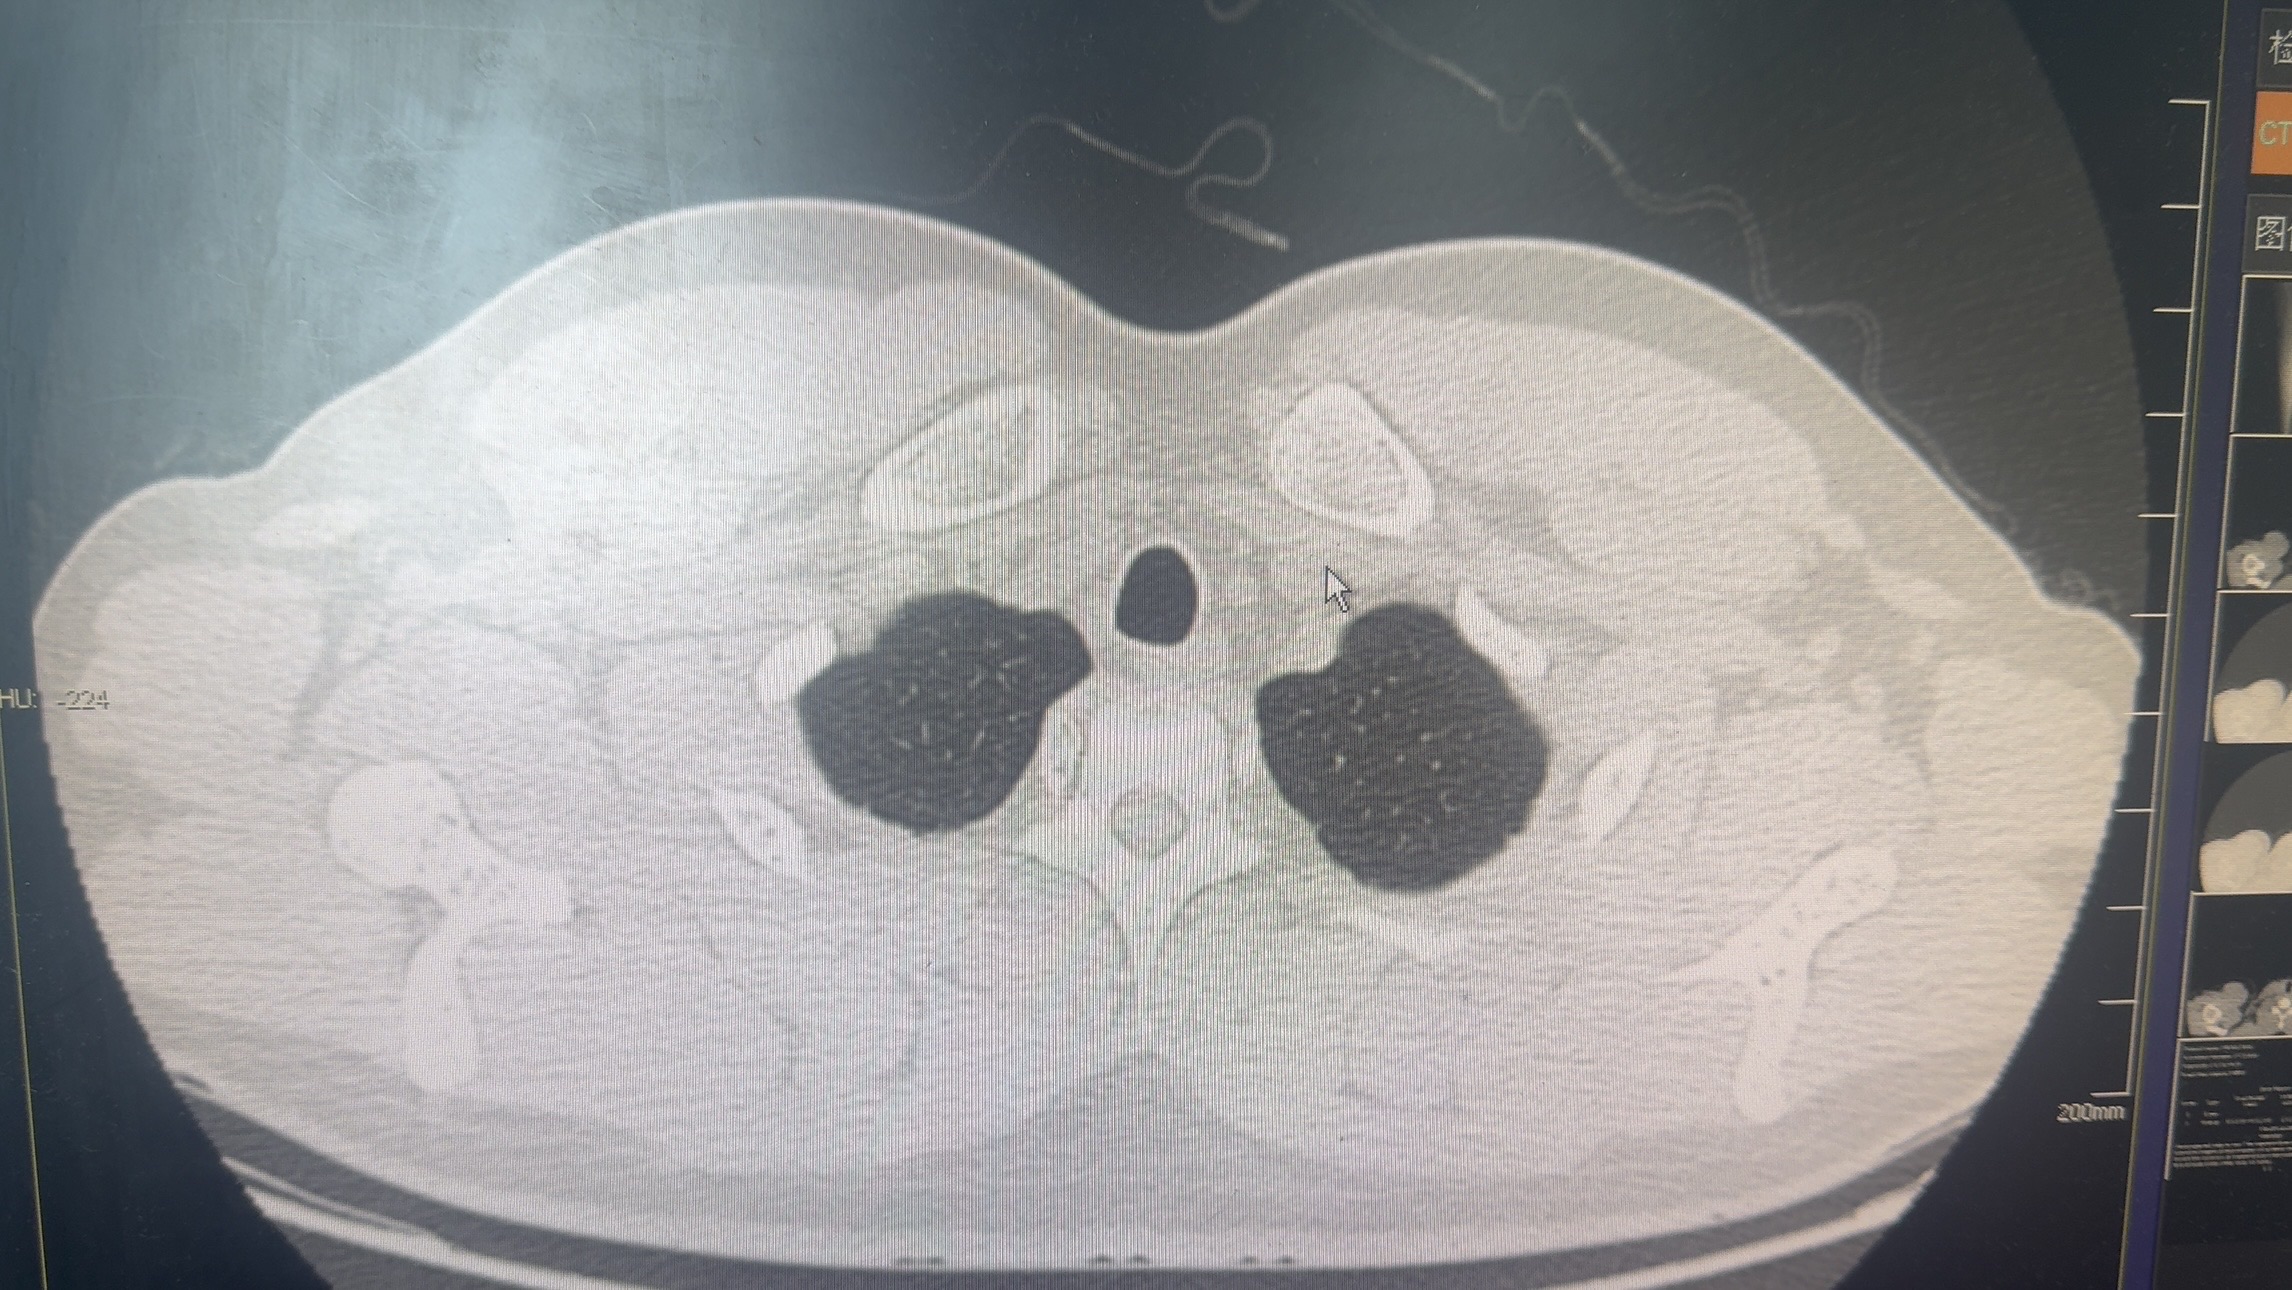

于6.26-7.3应用利奈唑胺600mg q12h,6.29-7.3头孢唑林2.0g q8h,体温未控制,仍每日出现发热,体温最高39度,遂停用利奈唑胺,7.4改用万古霉素1.0g q8h。用药3天后体温控制,患者7.9自动出院。出院第二天再次出现发热,体温40度。患者于6.29诉胸痛,复查ct

7.9复查ct示

7.12再次入院,继续给予万古霉素及头孢唑林治疗,7.17再次出现发热,7.17-7.22每日均出现发热,体温最高40度。7.18复查ct